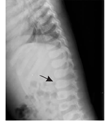

患儿,女,1岁8个月,因"毛发浓密1年余"于2017年10月就诊于武汉儿童医院遗传代谢内分泌科。患儿出生后毛发旺盛,颜色较黑,随年龄增长进行性加重,现多毛主要分布在颜面部、四肢、腰背部、臀部。无吐泻及抽搐,无发热,未行特殊处理。出生史:第2胎,第2产,足月,剖宫产,出生体质量4.55 kg,出生身长53 cm,头围37 cm。发育里程碑:3个月抬头、7个月萌牙、9个月会坐、1.5岁会走路及说话(现能说简单词,如爸爸妈妈、爷爷奶奶等)。身长84 cm(75th~90th)、体质量11 kg(50th~75th),头围51 cm,胸围44 cm,腹围46 cm,上部量55 cm,下部量39 cm。特殊面容,前额突出,较窄,耳位低,鼻梁塌,鼻头大,内眦赘皮,嘴唇厚,高颚弓,掌纹深(图1A、图1B)。皮肤色泽偏黑,皮肤弹性正常,毛发旺盛,主要分布在颜面部、额头、四肢、腰背部、臀部(图1C、图1D)。神志清楚,胸廓较窄,双肺未闻及啰音。心律齐,心音有力,未闻及杂音。腹部膨隆,触诊质软,无压痛及反跳痛,肝脏肋下1.5 cm,脾肋下未触及。四肢肌力及肌张力正常。双乳B1期,无乳头乳晕色素沉着,无阴毛、腋毛生长。父亲身高163.5 cm,母亲身高152.5 cm,遗传靶身高(152±4) cm。血尿便常规、肝肾功能、电解质、心肌酶谱、血脂、乳酸、血氨、骨碱性磷酸酶未见异常。甲状旁腺素33.7 ng/L。25羟维生素D 20.41 μg/L。胰岛素样生长因子-1<25.0 μg/L。生长激素1.15 μg/L。甲状腺功能正常。皮质醇上午8:00时611.05 nmol/L、皮质醇晚20:00时106.91 nmol/L、促皮质素22.8 ng/L。人绒毛膜促性腺激素0.19 IU/L,雌二醇53.67 pmol/L,睾酮0.14 μg/L,促黄体生成素0.01 IU/L,促卵泡生成素5.56 IU/L,泌乳素218.64 μIU/mL,孕酮0.12 μg/L。骨龄1岁6个月。心电图:窦性心动过速。彩超:肝右肋下1.6 cm,脾及双肾未见明显异常。卵圆孔未闭,左心室收缩功能正常。脊柱正侧位片:脊柱各段生理曲度及序列正常,L1-2椎体形态欠规则,椎间隙正常(图2)。四肢及头颅正侧位片:颅盖骨边缘光整,未见明显骨质病变征象。双侧肱骨及尺桡骨未见明显骨质病变,间隙正常。双股骨及胫腓骨未见明显骨质病变,髋膝关节间隙正常。肾上腺CT:未见明显异常。颅脑磁共振成像(MRI)平扫:未见明显异常。Gesell儿童发育量表:患儿一般发育水平约为16个月;患儿适应性、语言发育为边缘水平,其余各项发育正常。抽取患儿及患儿父母外周血2 mL,送北京金准基因科技公司进行全外显子测序。提取外周血白细胞DNA,采用KAPA LTP Library Preparation Kit试剂构建DNA文库。真空浓缩DNA文库样本进行杂交捕获,取捕获后的DNA样本进行高通量测序。所得到的基因变异再使用Sanger测序进行验证。经测序分析显示患儿ABCC9基因cDNA序列的第3 347位的鸟嘌呤突变为腺嘌呤(c.3347G>A),导致氨基酸精氨酸变为组氨酸(p.R1116H)。而父母均未携带(图3)。本研究通过医院医学伦理委员会批准(批准文号:武儿医2017020),患儿监护人知情同意,并签署知情同意书。